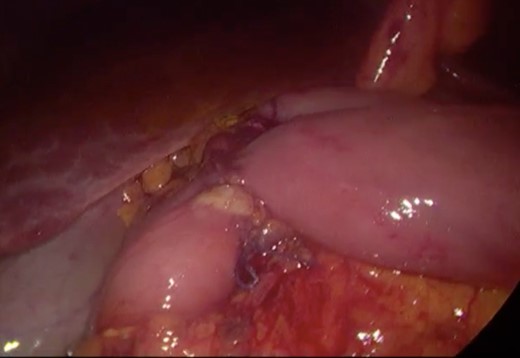

Initially, conservative management was adopted with some improvement of patient’s nutrition condition. However, as symptoms persisted, surgical treatment was recommended. Our surgical approach was a laparoscopic duodenojejunostomy with a latero-lateral stapled anastomosis between jejunum (30 cm from Treitz’s angle) and the second portion of the duodenum (Figs 5–9). The patient recovered with no pain but with a delay in diet acceptance. An upper GI contrast study was performed on the fifth post-operative day revealing a distended stomach with gastric emptying delay, but with unobstructed anastomosis, therefore without stenosis or leaks (Fig. 10). She was discharged home after 8 days with liquid diet and digestive transit restored. After 3 months of follow-up, the patient gained some weight and remained asymptomatic.

Surgery—laparoscopic stapled anastomosis between jejunum and second portion of duodenum.